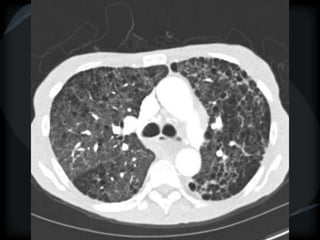

Reticular Pattern - NSIP

inflammation and fibrosis

 Predominantly basilar

 Significant ground glass

 Subpleural sparing low sensitivity, high specificity

 No honeycombing, some cystic change

 Traction Bronchiectasis

Diagnostic accuracy 50%

 Cellular NSIP

 Fibrotic NSIP

 Associated with CVD

 Undifferentiated CVD – T. King

NSIP- cellular

NSIP-fibrotic